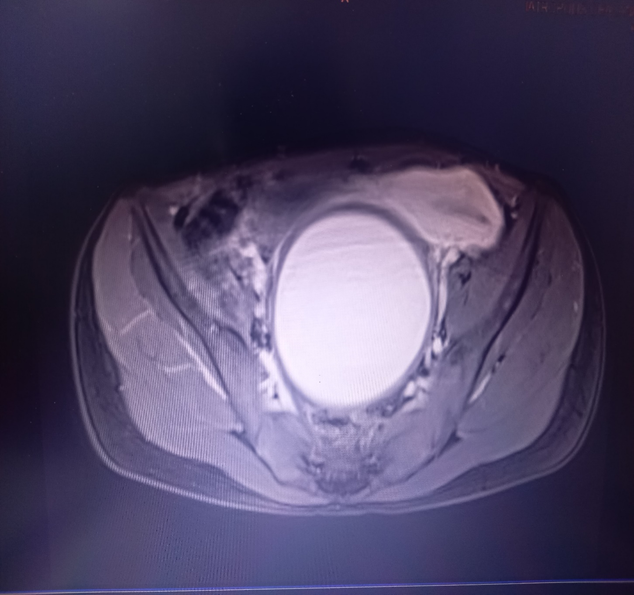

She underwent an abdominal magnetic resonance imaging (MRI) scan, revealing a distended vagina measuring 18.4 x 8.8 x 8.2cm, with a T1 hyperintense and T2 hypointense fluid collection suggestive of hemorrhagic fluid, consistent with hematocolpos. The uterus measured 5.3x5.6x3.5cm and was displaced anteriorly and to the left of the midline (Figure 2) (Figure 3). The rest of the abdominal and pelvic organs, including the kidneys, appeared normal.

Figure 2 Presence of hematocolpos (MRI scan: sagital section).

Figure 3 Presence of hematocolpos and displaced uterus (MRI scan: transverse section).